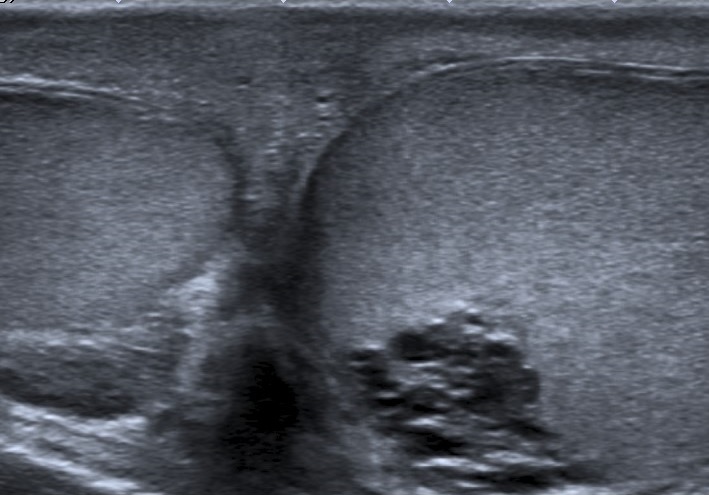

• Se realiza estudio con sonda lineal de alta frecuencia. Se explora el escroto y ambos testículos (figura 1), que presentan tamaño, morfología y ecoestructura normal, así como correcto flujo Doppler (figura 2). A nivel del teste izquierdo, se observa una colección de pequeñas imágenes anecoicas en el mediastino testicular, pseudotubulares. Además, una imagen anecoica, redondeada, quística, a nivel de la cabeza del epidídimo (figura 3).